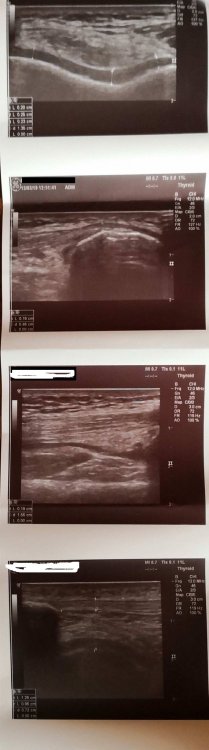

_GoGoL_ Napisano 13 Marca 2019 Napisano 13 Marca 2019 Cześć Sprawa wygląda tak. W 2017 miałem kontuzje kolana pod koniec sezonu koło września, przez jesień/zimę kiedy nie jeździłem, około 5-6 miesięcy uraz sie zagoił, ból przeszedł. Kiedy wsiadłem na rower w maju 2018 było cacy. Przejeździłem cały sezon, tylko tym razem sezon trwał dla mnie "non stop" bez względu na porę roku czyli innymi słowy jeździłem cały czas. Cały 2018 był OK, bez bólu, a kolano mocno zajeżdżałem, MTB/full i wszystko było super. Ból powrócił, tak naprawdę bez powodu w tym roku, 10 lutego podczas zwykłej wycieczki rowerowej. W tym samym miejscu bolesność co kiedyś. Efket? Panika bo wiedziałem ile ostatnim razem musiałem pauzować. Teraz jestem na dobrą sprawę "przed sezonem" wiosna/lato przed nami, a tu kontuzja A konkretnie wygląda to tak. Ból pojawia się TYLKO podczas ruchu pedałowania, wciskania pedałów w dół, innymi słowy przyspieszania. Zlokalizowany jest on po wewnętrznej stronie rzepki (zaznaczone na zdjęciu). Od 3 tygodni odpoczywam, nie forsuje kolana, nie jeżdżę na rowerze. Kilka dni temu wyszedłem sprawdzić czy coś się poprawiło - po 300m delikatny ból/dyskomfort w tym miejscu zaznaczonym na czerwono powrócił - wróciłem do domu. Na co dzień nie boli mnie wcale. Mogę normalnie funkcjonować. Miałem dziś robione USG tego kolana (zdjęcia w załącznikach opis/skan). Powiedzcie co robić? Jak leczyć "zdrowe" kolano? Ortopeda mnie już widział i póki co zlecił jedynie USG, które wykonałem. Czy spotkaliście się kiedyś z takim przypadkiem? Co byście sugerowali? Jakie kolejne kroki? Nie chcę być bierny i czekać miesiąc z nadzieją, że może samo przejdzie. Chce "zaatakować" temat i wyleczyć kolano najszybciej jak to możliwe. Info: Rower full, odpowiednio dobrana rama, geometria ok. Najbardziej oczywista kwestia to pozycja na rowerze, nie? Ale bądź tu człowieku mądry i zrób "bike fitting" na fullu, kiedy wysokość siodełka zmienia się cały czas względem pedałów.